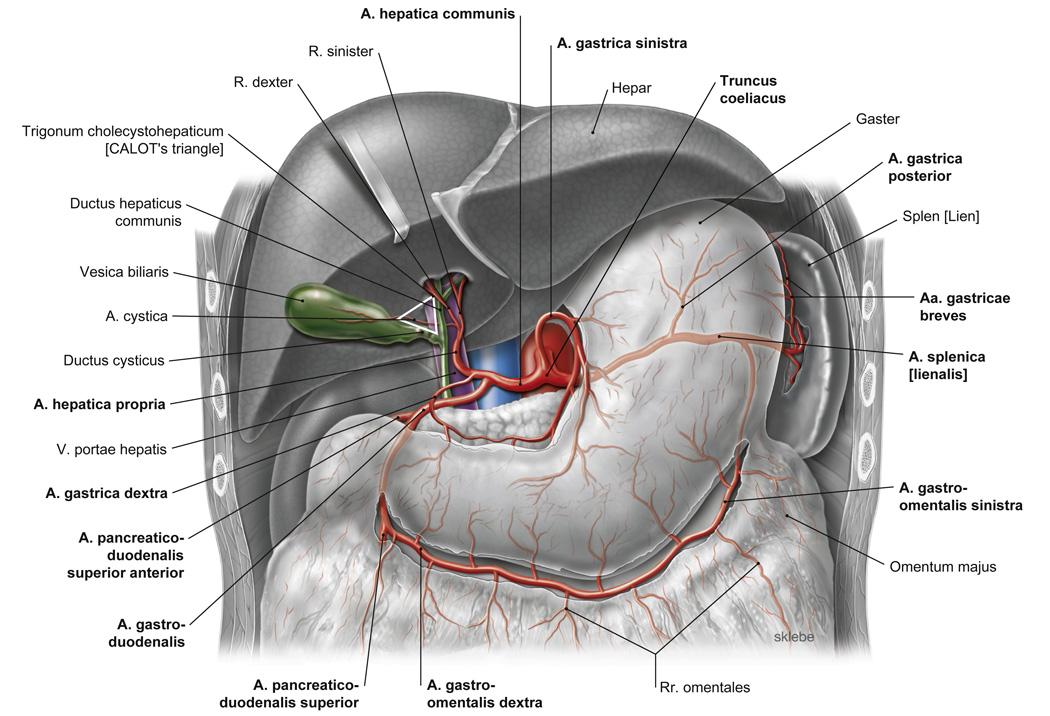

Fig 3.22: tr. coeliacus

diaphragma (groen) oesophagus -

ventriculus = maag

duodenum milt -

aorta abdominalis

|

|